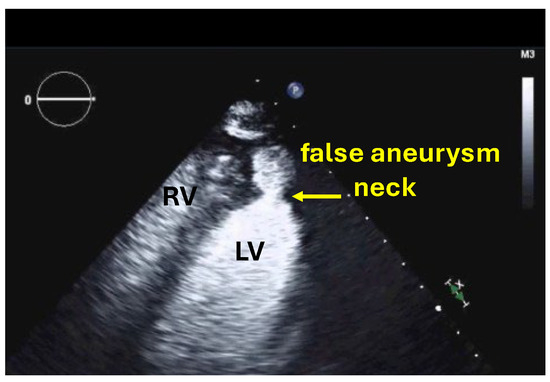

| Imaging method | Low-MI-contrast-specific imaging and intermediate-MI-contrast-specific imaging |

| Imaging planes | Standard apical views, zoomed apical views and modified/zoomed views |

| Sector depth/width | First assessment of the global and regional function using low-MI method and display of the entire LV + 1/3 LA, then zoomed views to display the region of the aneurysm |

| Focus | At the depth of the aneurysm |

| Gain | Adjust to avoid obscuring the LV borders by intensive opacification of the cavity |

| Contrast application | Bolus injection |

| Typical findings | Clear demarcation from the normal myocardium Narrow neck of false aneurysms Search for associated thrombi and pericardial effusion (more likely near false aneurysms) |

| Alternative imaging | Cardiac MRI or cardiac CT in patients with contraindications to UEAs or inadequate recordings with UEAs |